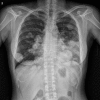

Hypocalcemia is relatively uncommon paraneoplastic syndrome. Only one case of hypocalcemia has been reported in a patient with chondrosarcoma. We herein report a case of a 32-year-old woman with metastatic chondrosarcoma with tetany. Her imaging findings revealed multiple calcific metastatic lesions in the lungs, pancreas, left atrium, and pulmonary vein. A laboratory examination showed hypocalcemia with no evidence of any other disease that could induce hypocalcemia. On the basis of the laboratory and clinical findings, we concluded the etiology of her severe hypocalcemia to be excessive calcium consumption by the tumor itself.